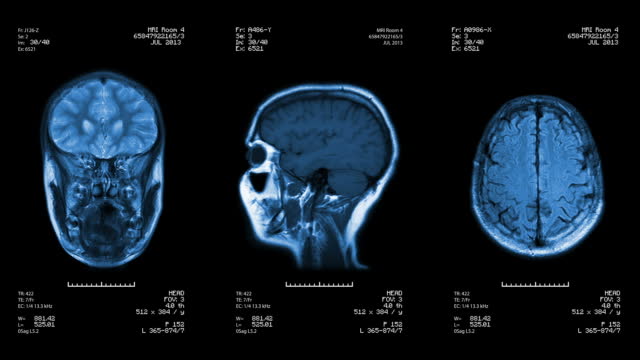

급성 뇌경색은 뇌 혈관이 막혀서 발생하는 중대한 질환 중 하나로, 우리나라에서 통계에 따르면 뇌경색의 약 1/4 정도는 아주 작은 뇌 혈관의 막힘으로 발생하며, 약 1/4 정도는 심장 질환과 부정맥과 관련이 있습니다.

또한, 5분의 1 정도에서는 경동맥이나 큰 뇌 혈관의 동맥경화로 인해 발생한다고 알려져 있습니다.

급성 뇌경색의 대표적인 증상은 한 쪽 팔과 다리의 마비, 한쪽 얼굴의 마비, 언어 장애 등입니다. 또한, 갑작스런 시력 감소나 어지러움과 같은 증상도 나타날 수 있습니다. 급성 뇌경색은 갑작스럽게 발생하므로 전조증상은 거의 없다고 볼 수 있습니다. 그러나 일관성 허혈 발전이라는 현상은 뇌경색과 유사한 증상이 나타나다가 몇 분 내에 사라지는 현상을 말합니다. 이런 경우에도 반드시 의료진의 진단과 조치가 필요합니다.